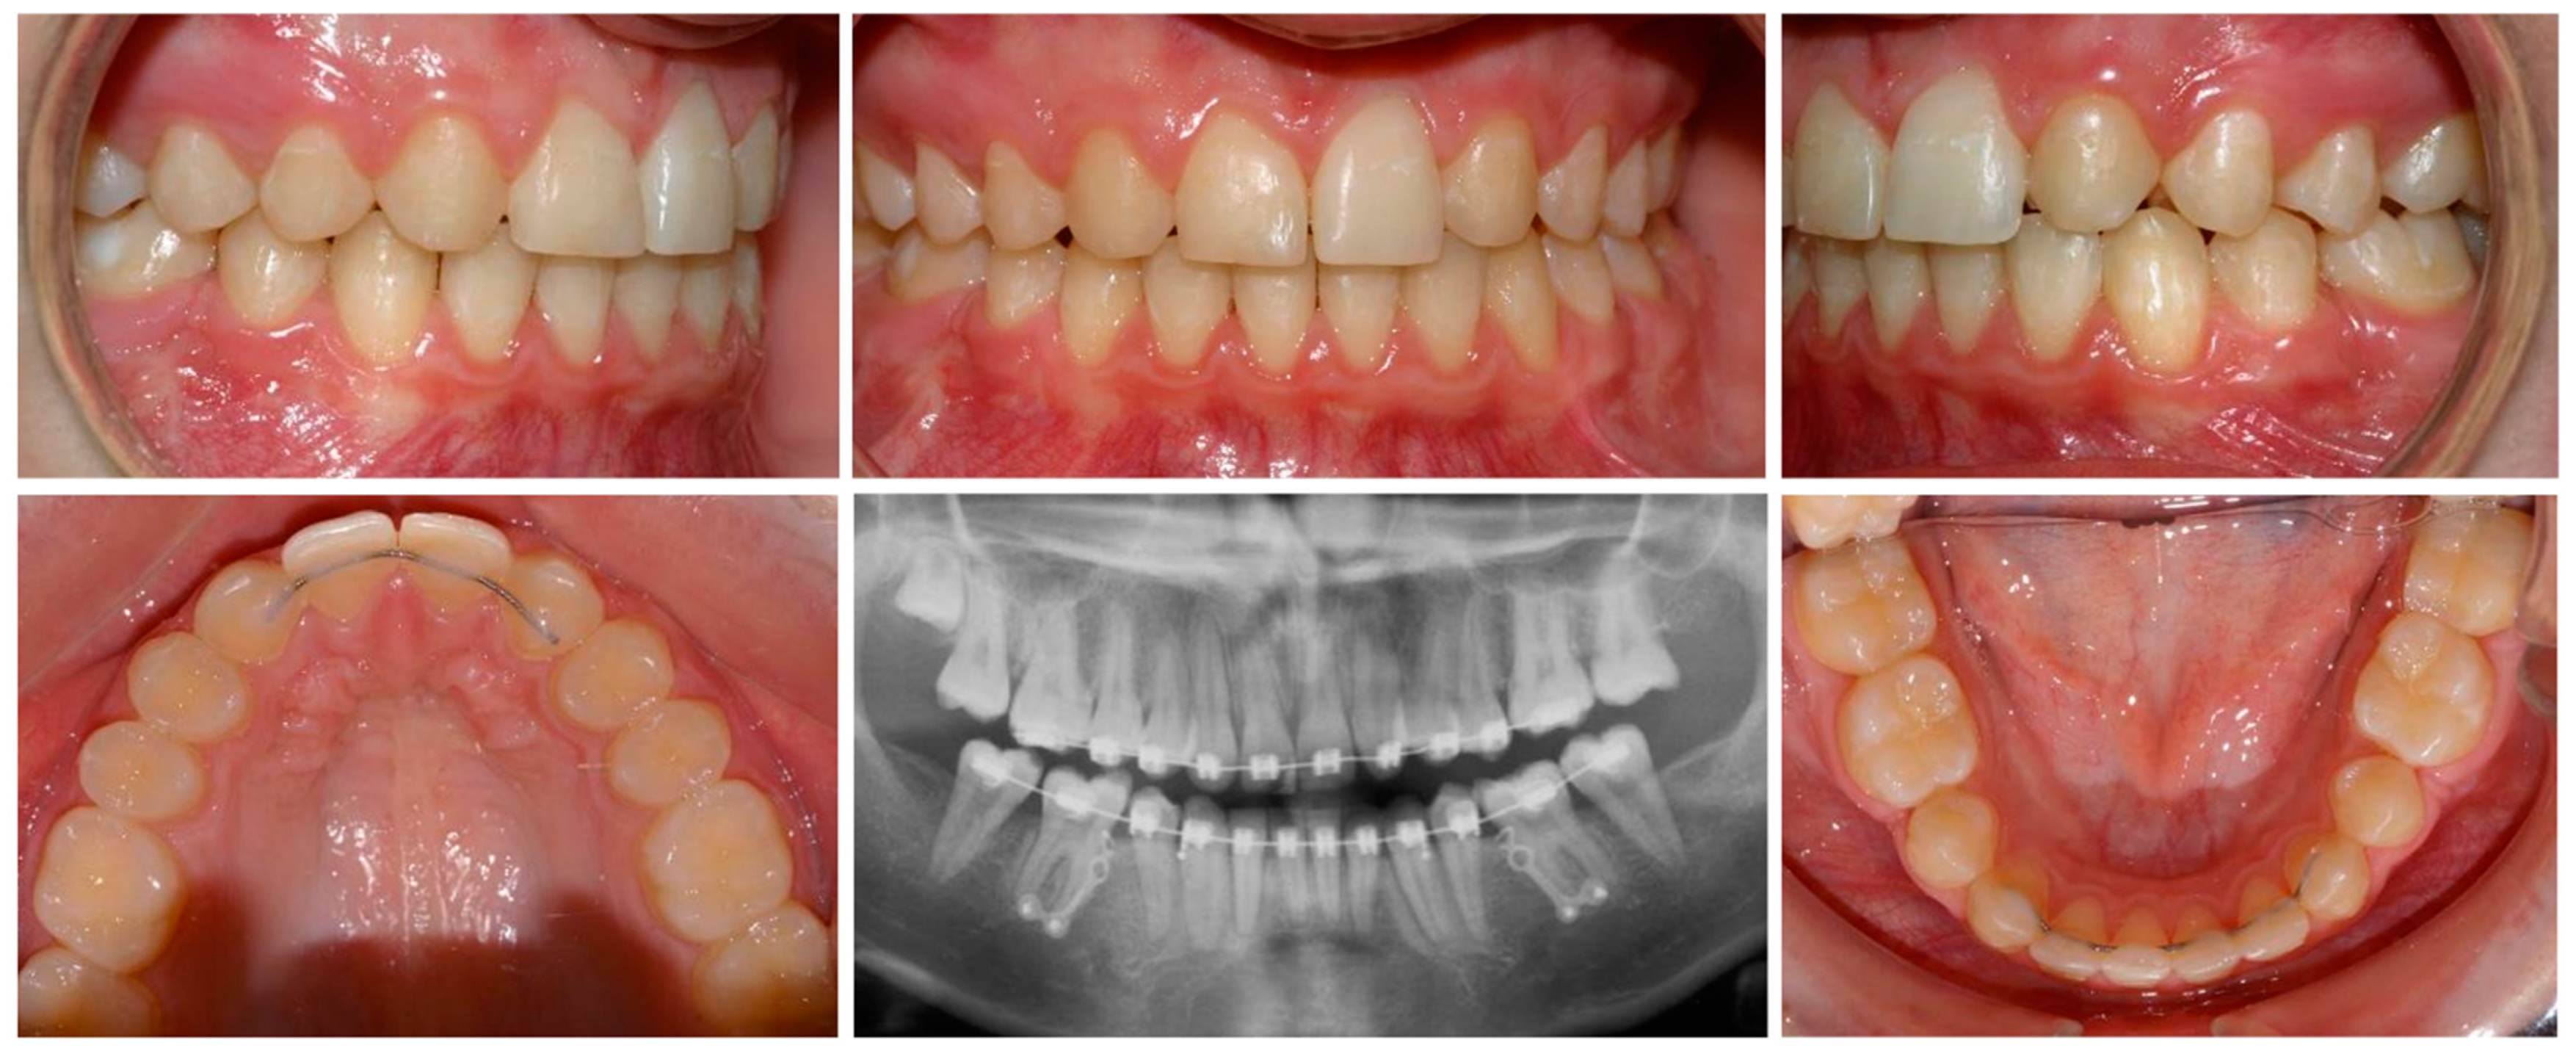

- To demonstrate the clinical management of agenesis of maxillary lateral incisors specifically, because of esthetic concerns, and that of missing second premolars.